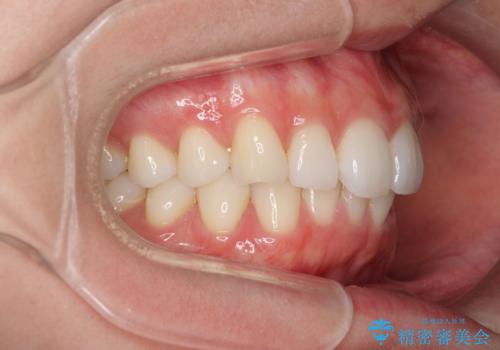

- 上下前歯の叢生を気にして来院された患者様です。

以前矯正をした後戻りということで、歯列不正はそれほど大きくなかったため、インビザライン・ライトを用いて矯正治療を行うこととしました。

前歯のデコボコが残っており、シミュレーション通りに動いていない部分がありましたが、再矯正であることやご本人の満足いくところまでデコボコが改善されたとのことで、治療を終了することとしました。